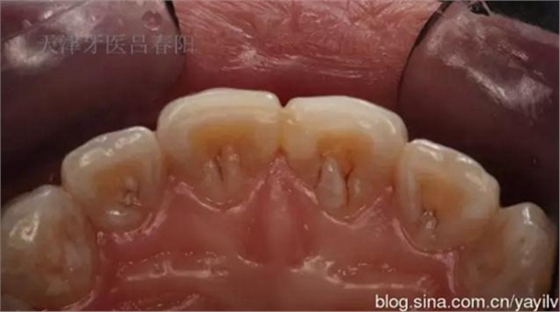

發(fā)一個最近完成的病例吧,雖然齲洞不大,但是挺好玩的,我自己認為。